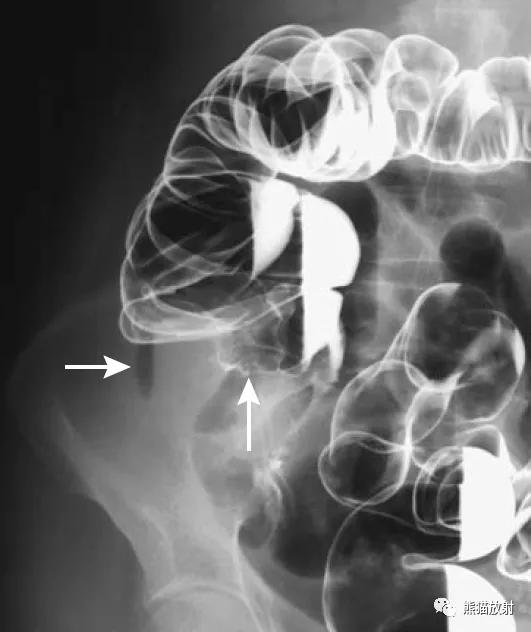

盲肠扭转。X线摄片显示中腹部肠管明显扩张(箭头)。钡餐检查示升结肠扭曲部位可见特征性的鸟嘴征(箭头)。

乙状结肠扭转。消化道造影侧视图可见乙状结肠局部走行扭曲(箭头)。